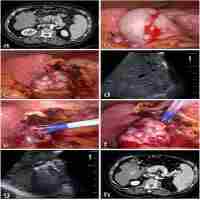

| Abstract | In China, the majority of patients with hepatocellular carcinoma (HCC) result from long-term infection of hepatitis B. Pathologically, HCC is characterized by rich blood supply, multicentric origins, early vascular invasion and intrahepatic metastasis. Therefore, HCC is not a local disease but a systemic disease at the beginning of its occurrence. For this reason, a comprehensive treatment strategy should be adopted in the management of HCC, including local treatments (such as surgical resection, radiofrequency ablation, microwave ablation, chemical ablation and cryoablation, etc.), organ-level treatments (such as transcatheter arterial infusion of chemotherapy and transcatheter arterial chemoembolization [TACE]), and systemic treatments (such as immunotherapy, antiviral therapy and molecular targeted therapy, etc.). This consensus sets forth the minimally-invasive and multidisciplinary comprehensive guideline of HCC, focusing on the following eight aspects: (1) find the intrahepatic lesion and make precise staging; (2) TACE combined with ablation or ablation as the first choice of treatment for early stage or small HCC; (3) infiltrating HCC should be regarded as an independent subtype of HCC; (4) minimally-invasive comprehensive treatment could be adopted in treating metastatic lymph nodes; (5) multi-level subdivision of M-staging should be used for individualized treatment and predicting prognosis; (6) HCC with severe hepatic decompensation is the only candidate criterion for liver transplantation; (7) bio-immunotherapy, traditional Chinese medicine therapy, antiviral therapy, and psychosocial and psychopharmacological interventions should be advocated through the whole course of HCC treatment; (8) implementation of multicenter randomized controlled trials of minimally-invasive therapy versus surgery for early and intermediate stage HCC is recommended. |